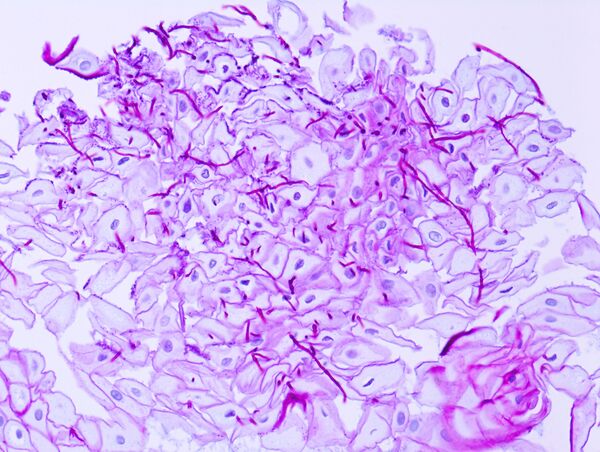

| Эрозивная форма | Чаще всего развивается при острых инфекционных болезнях и действии на стенку пищевода раздражающих веществ. |